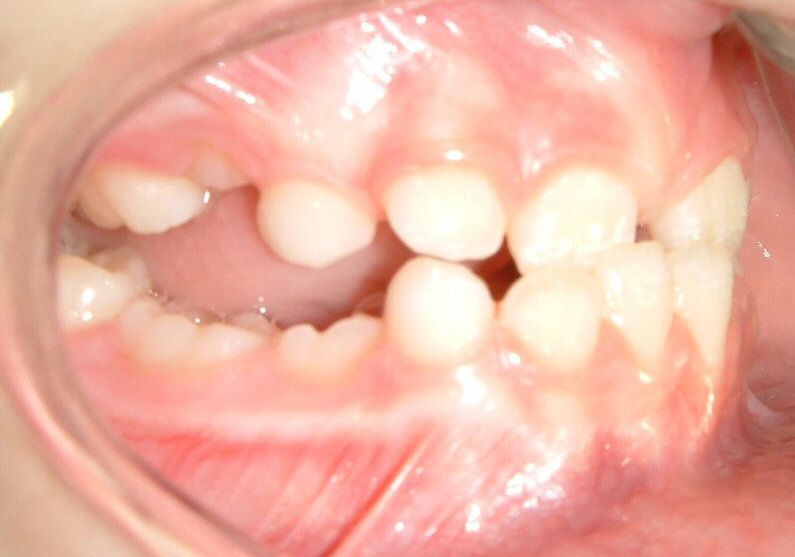

Case 2: 8 yr-old female (without extraction)

Fig. 5 View showing ovejet (initial)

© Copyright 2007-2014, Vu Orthodontics. All rights reserved.

Fig. 6 View showing progress (6 months)

© Copyright 2007, Vu Orthodontics. All rights reserved.